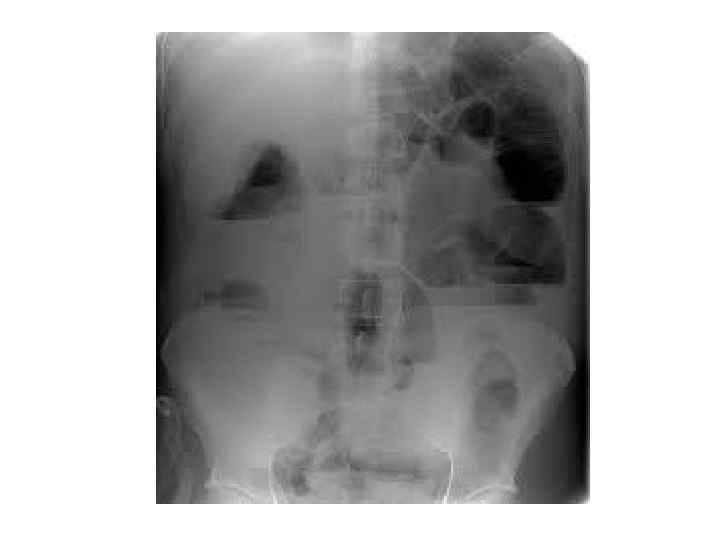

• Рентгенография брюшной полости: определение газа и уровней жидкости в петлях кишок (чаши Клойбера) поперечная исчерченность кишки (симптом керкринговых складок) • УЗИ: • при механической кишечной непроходимости: расширение просвета кишки более 2 см с наличием феномена «секвестрации жидкости» в просвет кишки; утолщение стенки тонкой кишки более 4 мм; наличие возвратно поступательных движений химуса по кишке; увеличение высоты керкринговых складок более 5 мм; увеличение расстояния между керкринговыми складками более 5 мм; гиперпневматизация кишечника в приводящем отделе • при динамической кишечной непроходимости: отсутствие возвратно поступательных движений химуса по кишке; феномен секвестрации жидкости в просвет кишки; невыраженный рельеф керкринговых складок; гиперпневматизация кишечника во всех отделах

Повреждение полых органов быстро осложняется перитонитом, который про является сухостью языка, тахикардией, пострадавший щадит брюшную стенку при дыхании, пальпация выявляет напряжение брюшной стенки и выраженную болезненность, симптом Щеткина—Блюмберга положителен. При разрыве полого органа в брюшную полость поступает свободный воздух, который скапливается под диафрагмой, что при перкуссии создает впечатление сглаженной печеночной тупости.